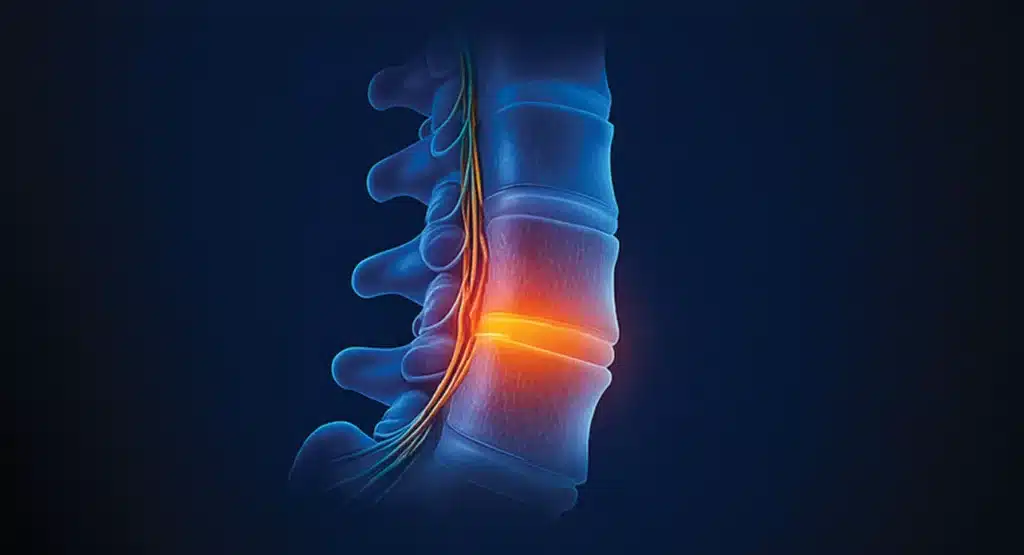

Herniated disk

หมอนรองกระดูกสันหลังเคลื่อนออกเมื่อแกนกลางที่มีลักษณะคล้ายวุ้นดันกับวงแหวนด้านนอก เมื่อหมอนรองกระดูกสันหลังเคลื่อนออกไปยังช่องไขสันหลัง อาจกดทับเส้นประสาทไขสันหลังที่ไวต่อความรู้สึก ทำให้เกิดอาการปวด

หมอนรองกระดูก (Intervertebral Disc) ทำหน้าที่เหมือนเบาะรองระหว่างกระดูกสันหลัง เมื่ออายุมากขึ้น หรือใช้งานหนัก หมอนรองกระดูกจะสูญเสียน้ำและคอลลาเจน ทำให้ “ความยืดหยุ่นลดลง” ผลคือเกิดการกดทับเส้นประสาท → ปวดหลัง ร้าวลงขา หรือชาบริเวณขา